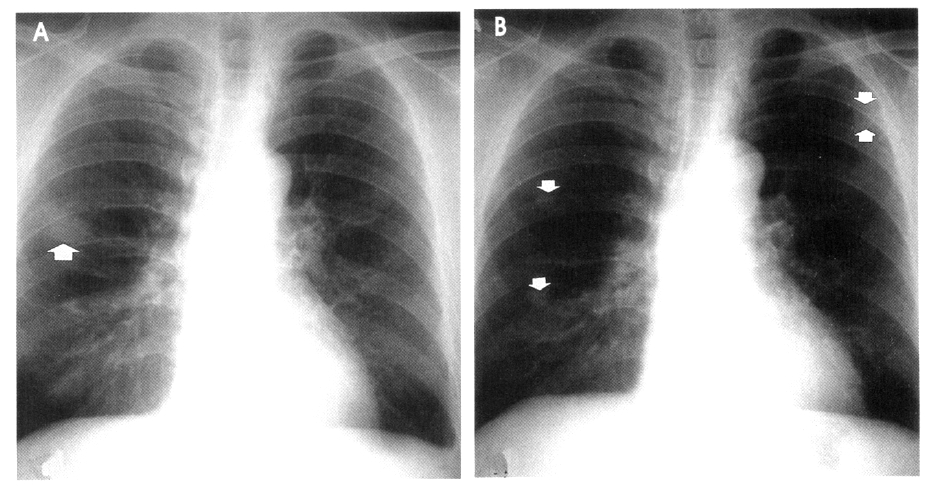

Serial chest radiography (Figure 2A, 2B) and high resolution computed tomography (Figure 3A, 3B, 3C) showed that the pulmonary nodules and patchy densities migrated to other sites and changed in shape and size daily. On the second day of admission, the patient underwent fiberoptic bronchoscopy that revealed no endobronchial lesion. The bronchoalveolar lavage (BAL) fluid had cell proportions of 45% macrophage 15% lymphocytes, 15% neutrophils, and 25% eosinophils (Figure 4). The BAL fluid was negative for bacterial, acid-fast bacilli, and fungi. A transbronchial lung biopsy was performed at the right middle lobe. Microscopy of the lung tissue showed eosinophilic infiltration (Figure 5). Abdominal ultrasound revealed no specific abnormalities except mild splenomegaly. On the ninth day of admission, migrating nodular densities on chest radiographs decreased and then disappeared dramatically following oral praziquantel therapy (Figure 6). Blood eosinophilia consequently decreased and normalized. There was no evidence of recurrence after one year of follow-up.

Figure 2.

Serial chest radiographs, at second hospital day (A), 4th day (B) show nodular and patchy densities that migrate to different sites and change in size and shape (arrows).